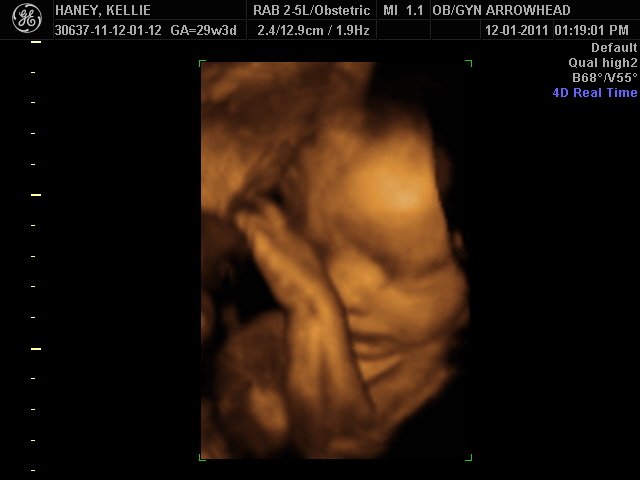

We offer complimentary 3D/4D Ultrasounds to all our OB patients around 30 weeks! The following photos are some examples of our work, shown with permission from our patients.